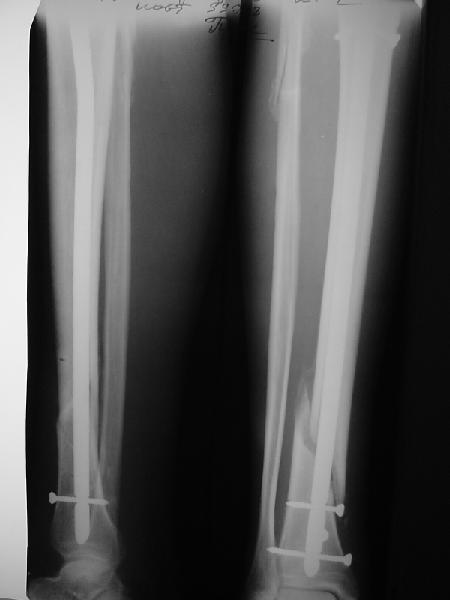

Ok. А также и следующий, в 3 месяца.

Это наглядная демонстрация возможности ранней полной нагрузки при нестабильном по оси повреждении, причем не в самых благоприятных механических условиях - при плохом сопоставлении, со слабым фиксатором.

Как я уже говорил, мы сделали выводы из этого и других подобных случаев. Очевидно, решений проблемы два - либо уменьшить нагрузку, либо увеличить прочность фиксатора. Первое решение работает не со всеми больными, так что пошли по второму пути - мы больше не используем гвозди с запирающими винтами диаметром 4 мм.

Что именно показать? Что пациент может стоять на больной ноге к 1 месяцу? При интрамедуллярном остеосинтезе по поводу ложных суставов, когда мышцы давно зажили, это и на 3-5 день наблюдается. В чем именно Вы сомневаетесь? Что гвоздь диаметром 12-13 мм с винтами более 5 мм способен нести полную нагрузку? Или что ходить без хромоты можно только после рентгенологического сращения? Или?..